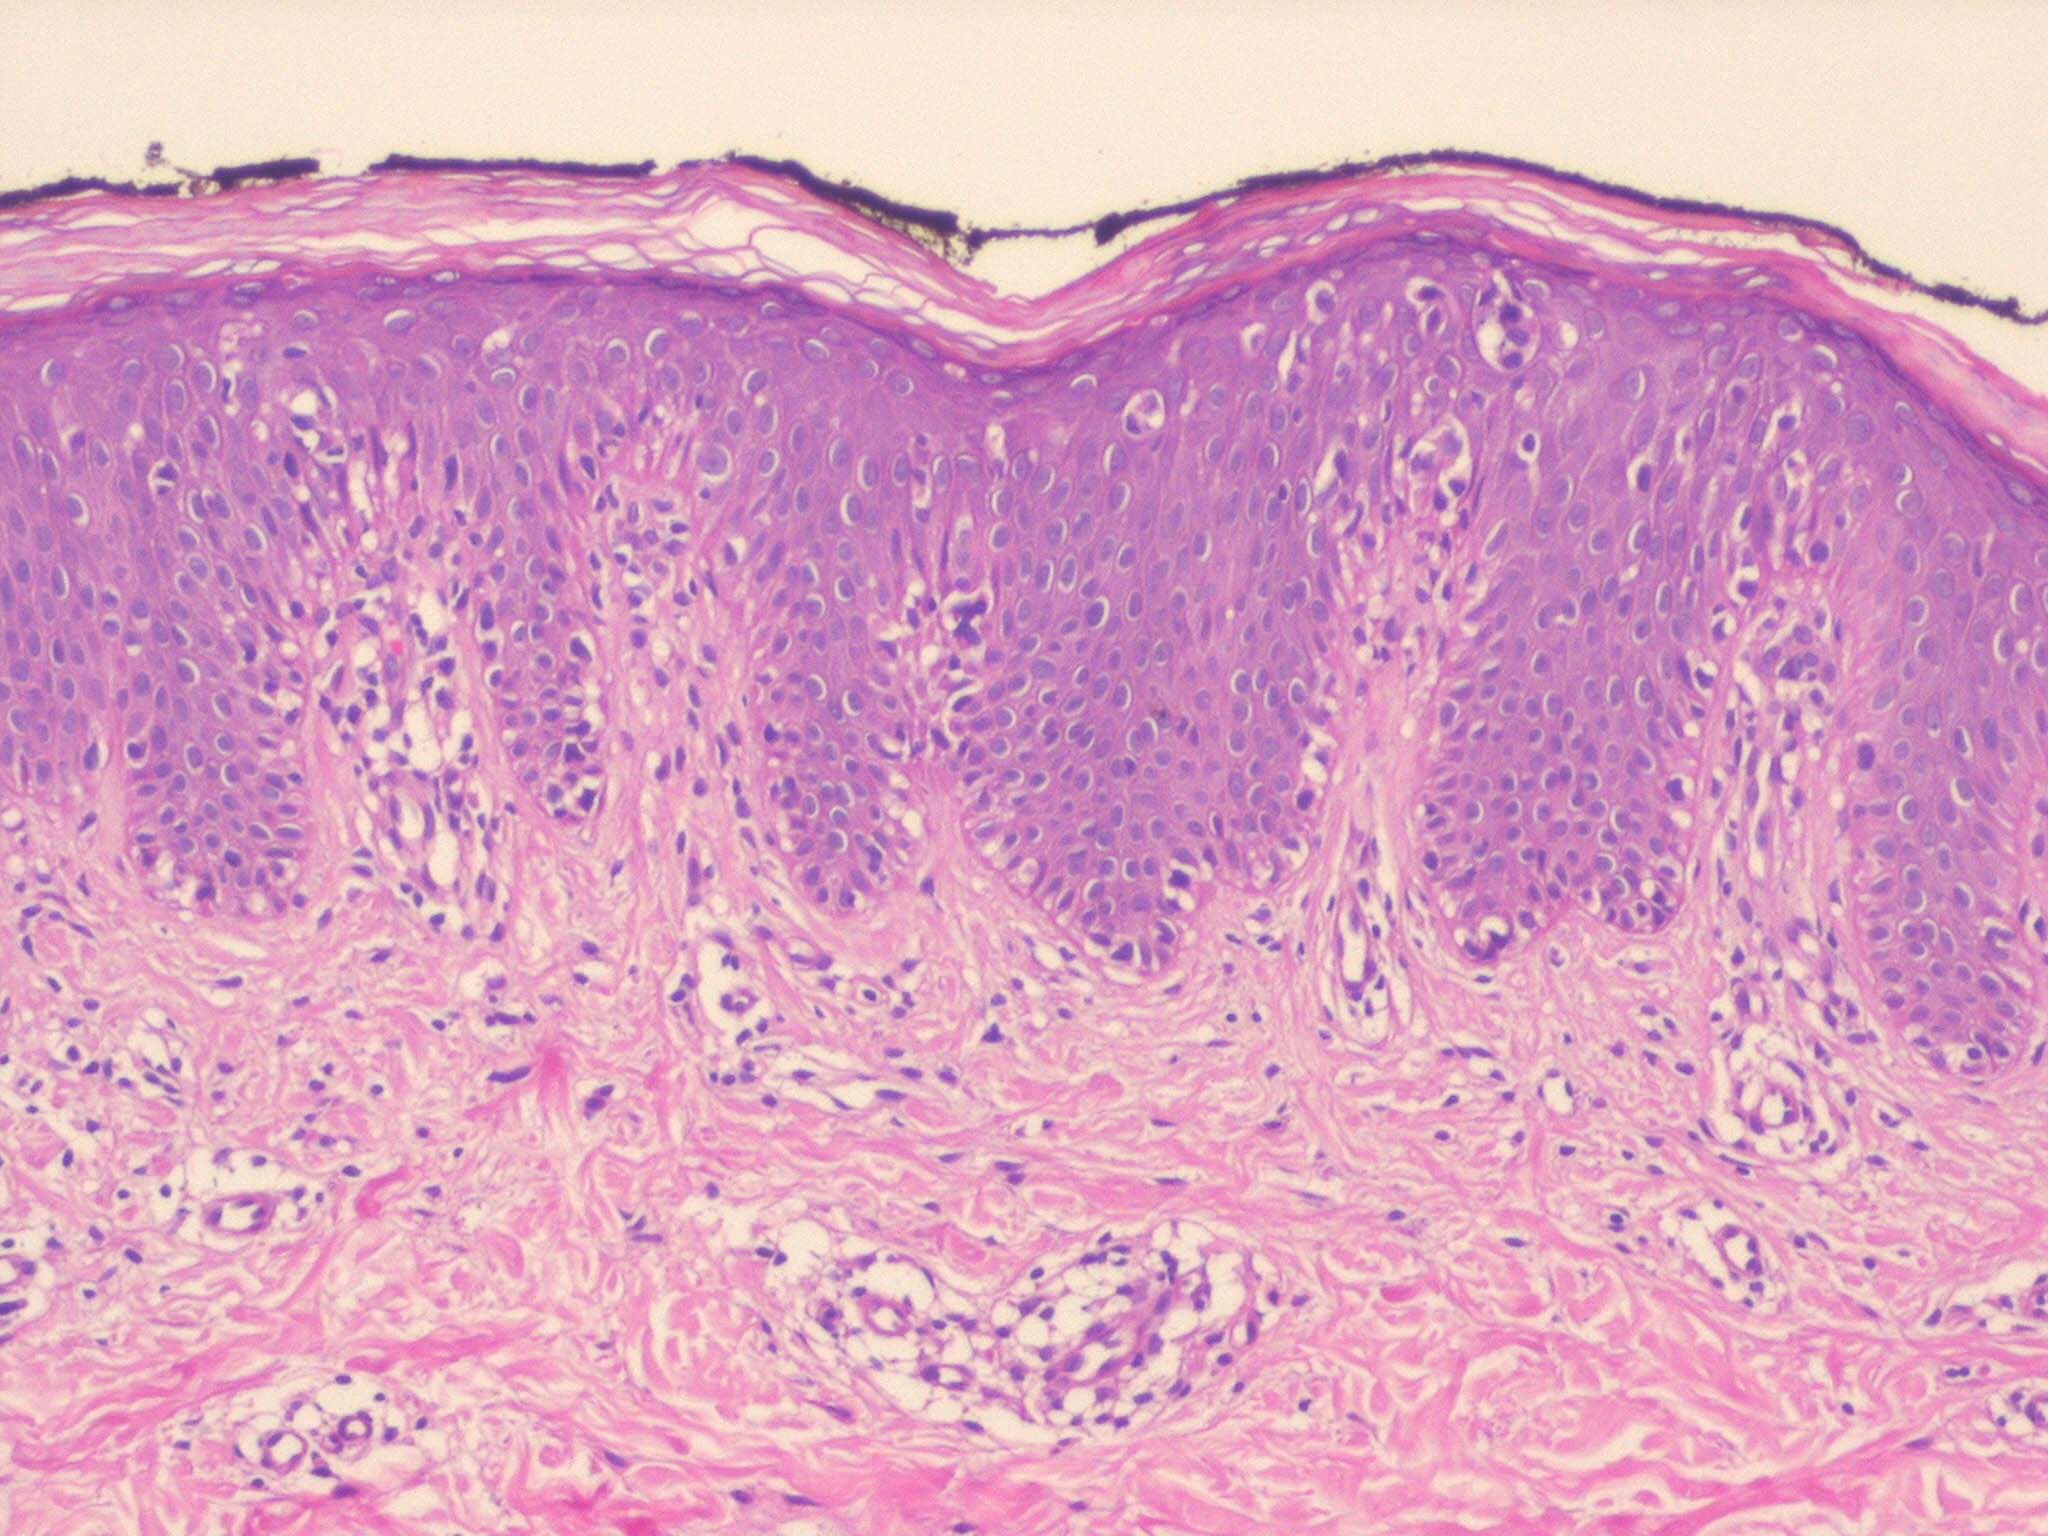

Mycosis Fongoïde =التفطر الكمئي